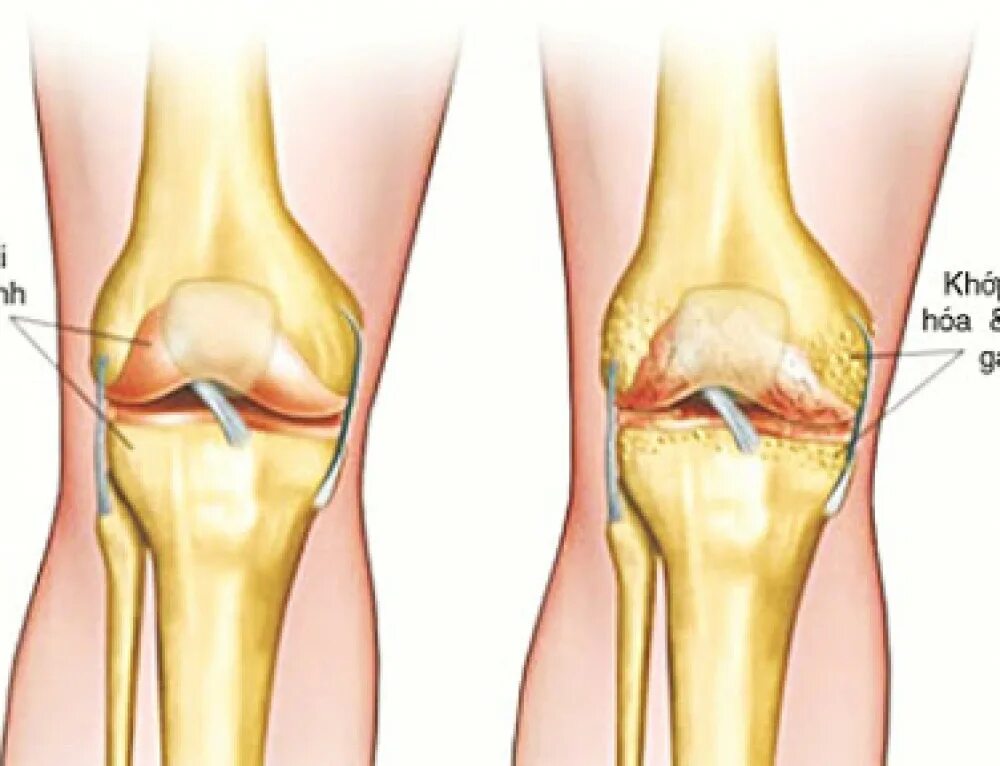

Артрит суставов стадии